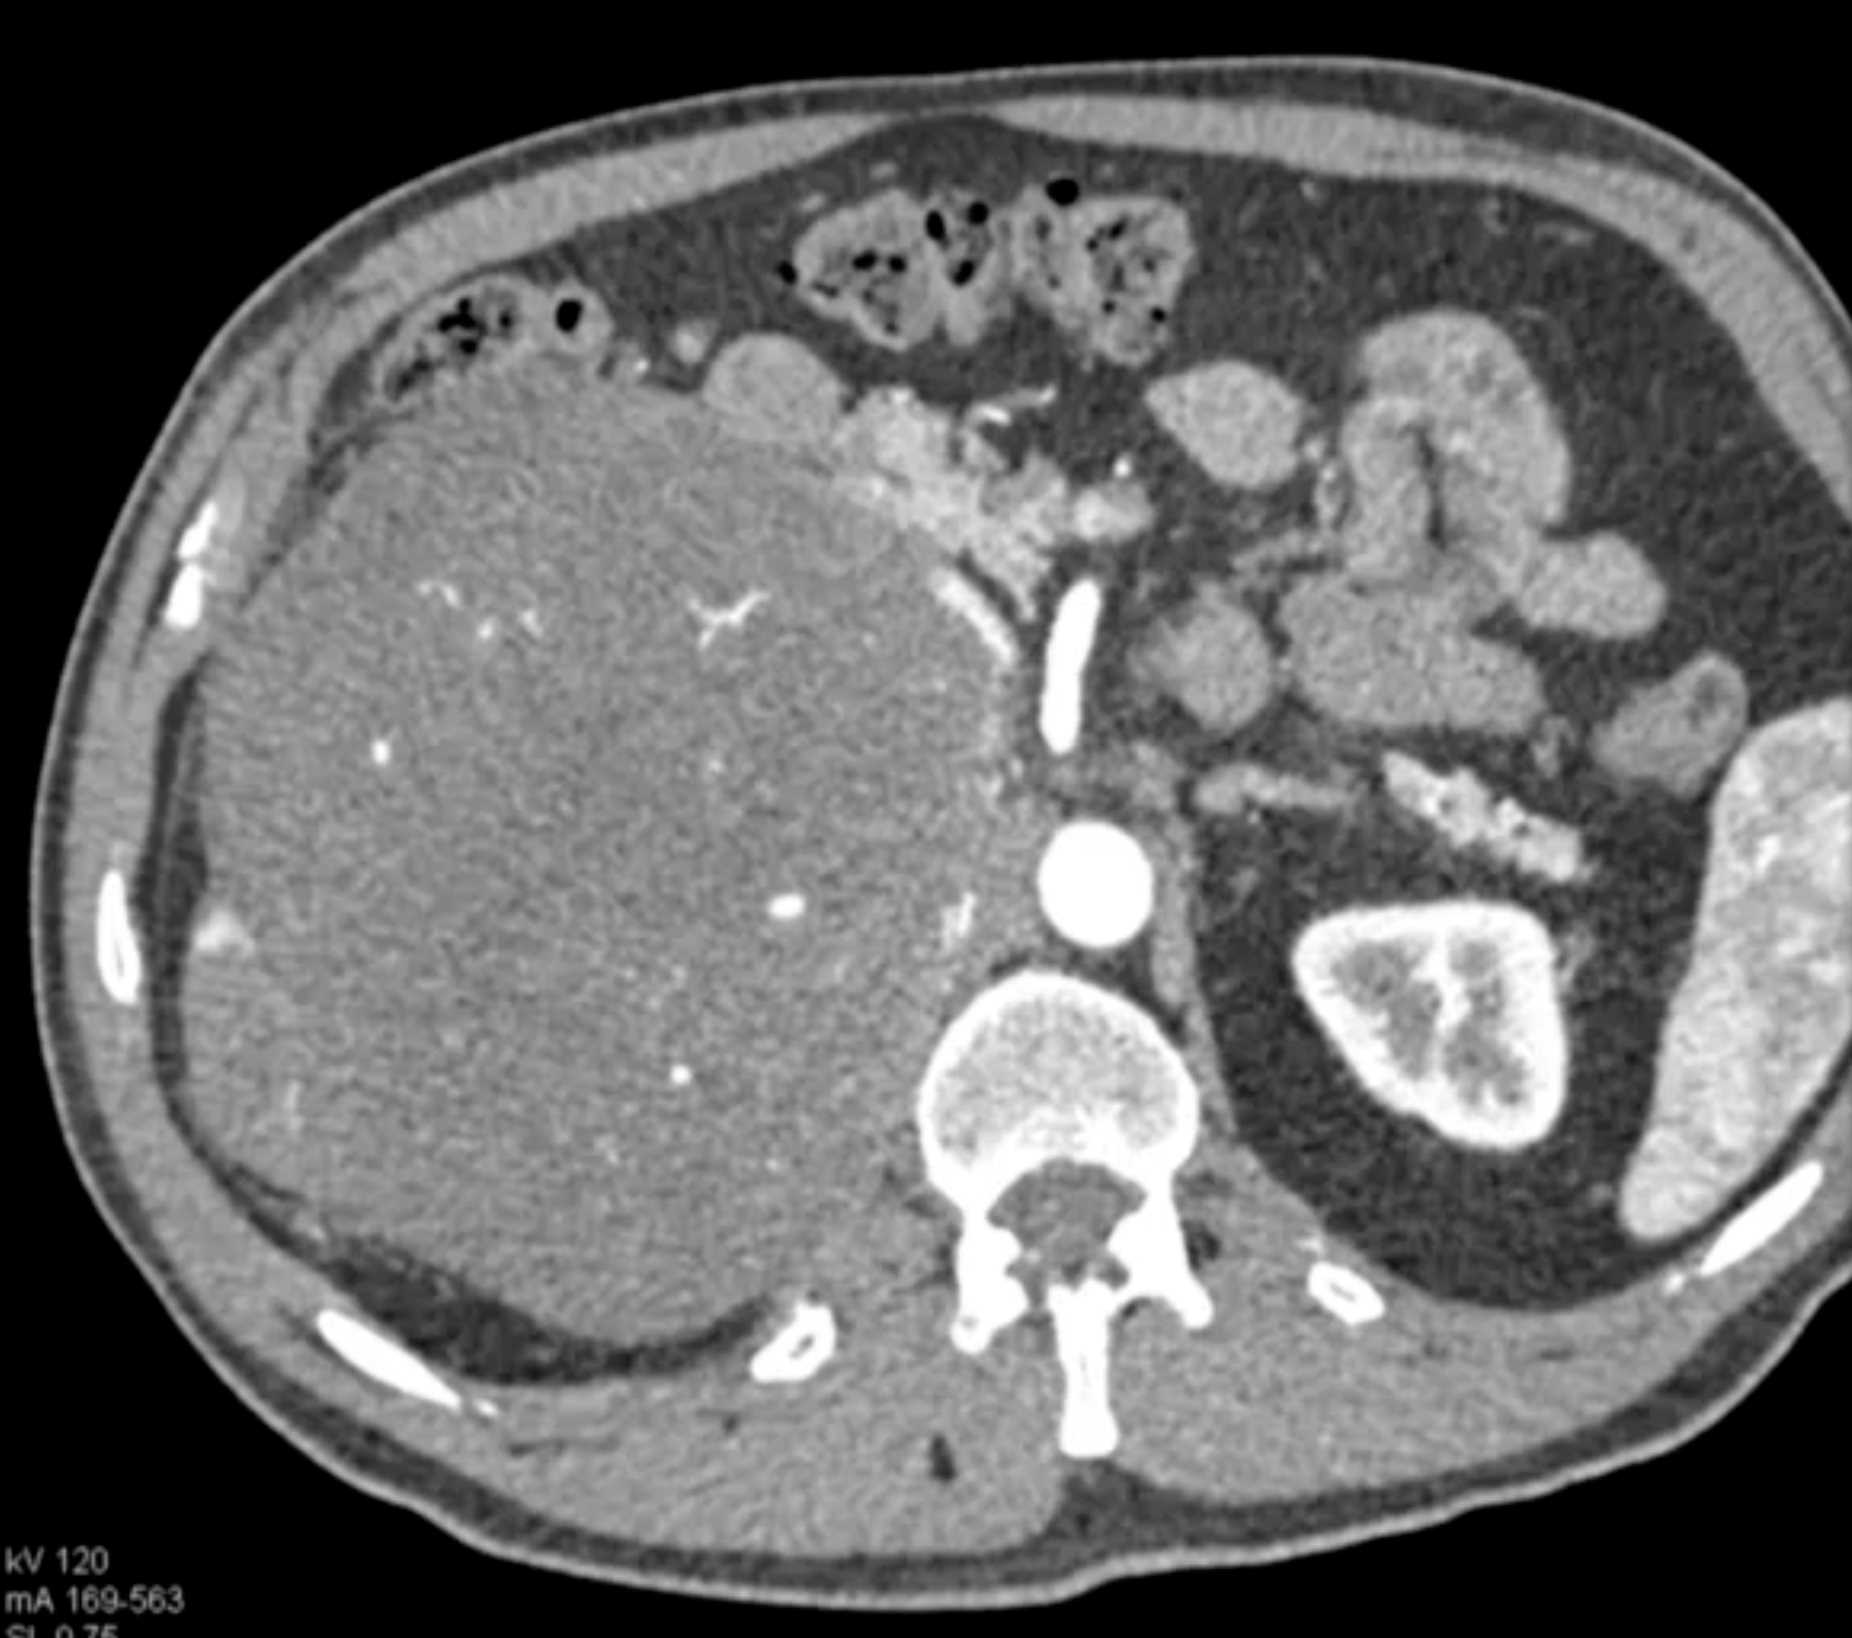

Left Adrenal Metastases from Renal Cell Carcinoma